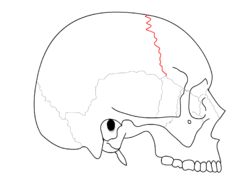

Trajectory of the missile through President Kennedy's skull. The bullet struck posterior part of his right parietal bone from behind.- Cephalic extremity.Original mummification.